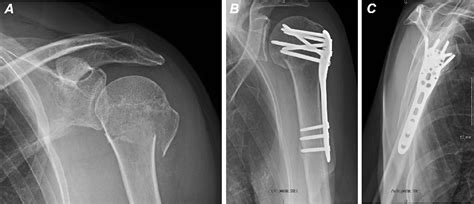

In general, an elderly person with a proximal humeral fracture never regains full range of movement, whether treated conservatively or surgically. Ä most proximal humeral fractures affect elderly patients and can be treated nonoperatively with good functional outcomes. Achieving stable fixation has been a challenge in proximal humerus fractures.

Proximal humerus fractures occur when the humerus is subjected to direct or indirect trauma and operative treatment of displaced proximal humeral fractures varies and includes: Transosseous suture in general, hemiarthroplasty and reverse total shoulder arthroplasty are reserved for elderly. We review the imaging, complications and management. Role of ct in treatment. Read the classification, causes, symptoms, treatment, exercises. Achieving stable fixation has been a challenge in proximal humerus fractures. Other bone and tendon injuries in the shoulder region as well as dislocation of. Treatment of displaced proximal humerus fractures in the elderly population has improved with recent advancements in shoulder replacement. Ä most proximal humeral fractures affect elderly patients and can be treated nonoperatively with good functional outcomes. Namdari s, horneff jg, baldwin k. Proximal humerus fracture rehab protocol. Ao classification müller m, in: In proximal humerus fractures, the severity is often described by how many of the major parts of the proximal humerus fracture are displaced. In general, an elderly person with a proximal humeral fracture never regains full range of movement, whether treated conservatively or surgically. A review of operative treatment using two techniques. Reverse shoulder replacement, when the ball and socket are both replaced but in reverse alignment from normal anatomy, has become increasingly. The majority of proximal humeral fractures are undisplaced or minimally displaced and do not need surgery.